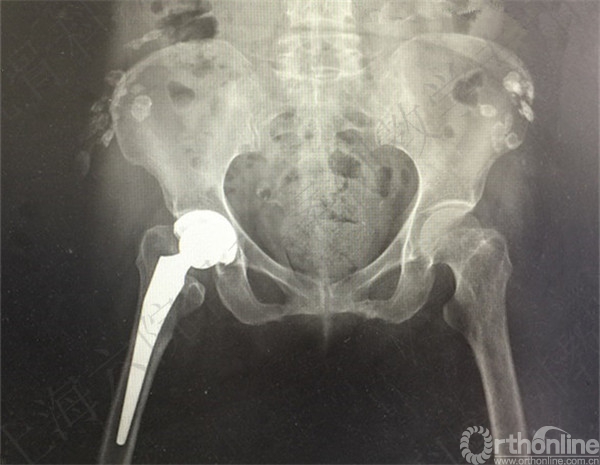

术后X线摄片示:假体在位,骨折对位对线可。

此类患者依从性较差,第一次术后医方应充分告知,嘱咐并强调相关注意事项,必要时转下级医院继续康复治疗。假体脱位手法复位后,未能明确排除是否存在假体松动。医方存在对术后并发症观察、处理不当,告知缺陷等过失。